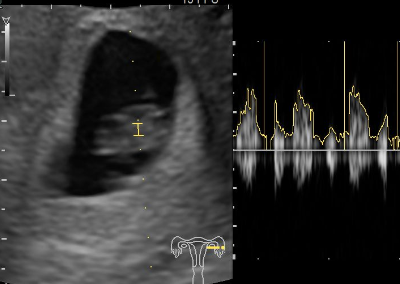

胎芽はどんどん大きくなります。脳や心臓、手足などさまざまなパーツが形成され始めます。赤ちゃんの心拍がはっきりと見えてくるころです。